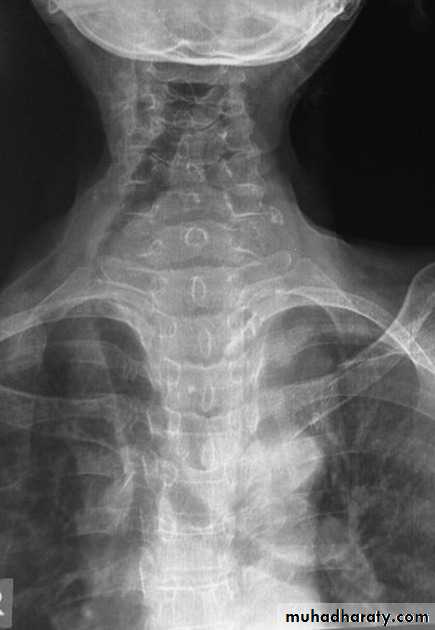

Retrosternal goiter

Radiographic featuresChest radiograph

It may show a superior mediastinal radio-opacity causing the deviation of trachea to opposite site. The superior margin of the radio-opacity/mass is untraceable (cervicothoracic sign).